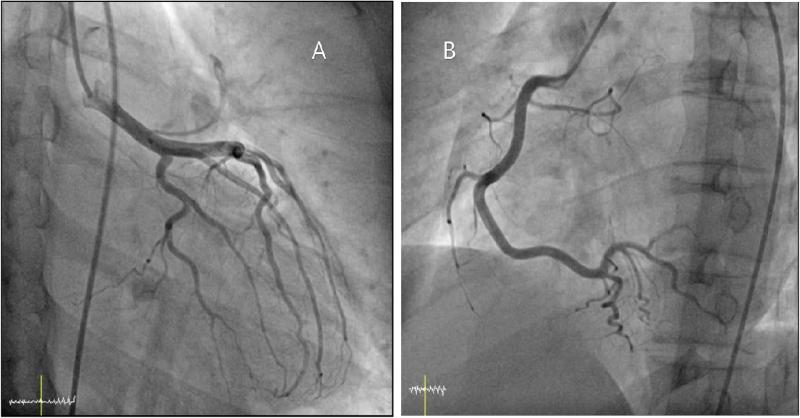

- Acute myocarditis leading to Coronary artery spasm in an adolescent

Inflammation caused by infection or autoimmune disease of the myocardium is known as Myocarditis. This causes cell death and injury due to inflammation that further causes structural and functional cardiac abnormalities presenting with or without clinical manifestations such as gastrointestinal symptoms, dyspnea, chest pain, or sudden death. The di

Acute myocarditis leading to Coronary artery spasm in an adolescent